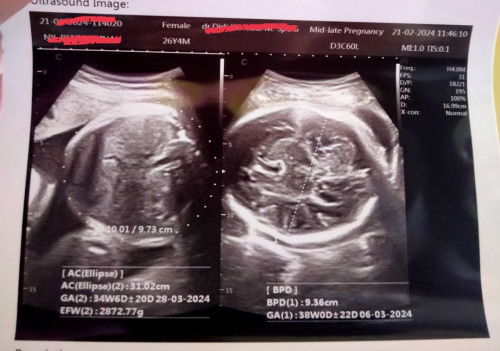

AC 35week, BPD 38week

Bund normal ga kalo Ac 35week, BPD 38week, worry soalnya anak pertama takut kenapa2 #sharing #bantujawab

Usia BPD lebih 3mingu dari GA

Usia 35week tapi BPD menunjukan usia 38week. Itu kira2 gmna ya bund? Normal atau nggak? Tolong di sharing2 bund worry anak pertama😭😭😭